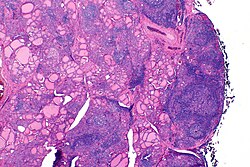

![]() Histologiya | |